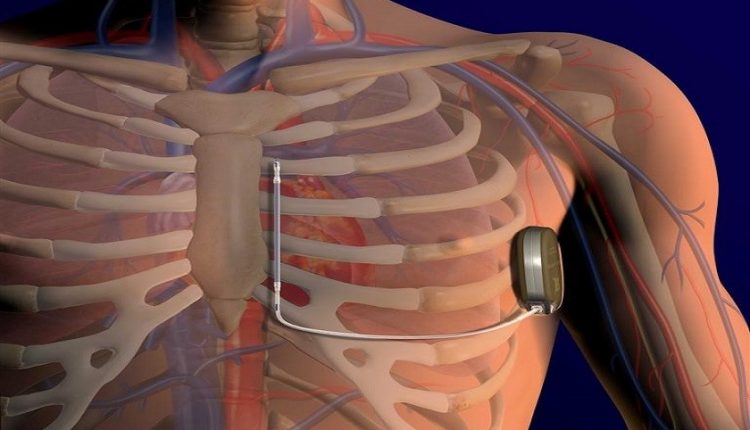

Širdies stimuliatorius – maždaug 2 eurų monetos dydžio elektros prietaisas – dedamas krūtinės ląstos srityje, po raktikauliu.

Jis yra prijungtas prie vieno ar dviejų laidų (laidų), kurie savo ruožtu susisiekia su širdies raumeniu.

Laidai perduoda informaciją iš širdies stimuliatoriaus į širdį ir prireikus siunčia elektrinius impulsus.

Širdies stimuliatorius programuojamas specialiu kompiuteriu, kurio dėka specialistas gali peržiūrėti visą informaciją apie paciento širdį ir jos veiklą.

Poodinis defibriliatorius implantuojamas taip pat, kaip ir širdies stimuliatorius

Pirmoji dalis yra susijusi su laidų išdėstymu, ty „elektros laidais“, kurie pasiekia širdį. Jų skaičius gali svyruoti nuo vieno iki trijų, priklausomai nuo implantuojamo prietaiso tipo.

Laidai įvedami į veną (poraktinę arba galvinę, dažniausiai kairiąją).

Patekę į venų sistemą, laidai nustumiami į širdies kameras (dešinįjį skilvelį, dešinįjį prieširdį, vainikinį sinusą) ir dedami tose vietose, kur jie geriausiai jaučia širdies veiklą ir taip gali stimuliuoti širdį su mažiausia energija.

Patikrinus kateterių stabilumą ir elektrinius parametrus, laidai pritvirtinami prie apatinio raumens, o po to prijungiami prie defibriliatoriaus, kuris dedamas po oda.